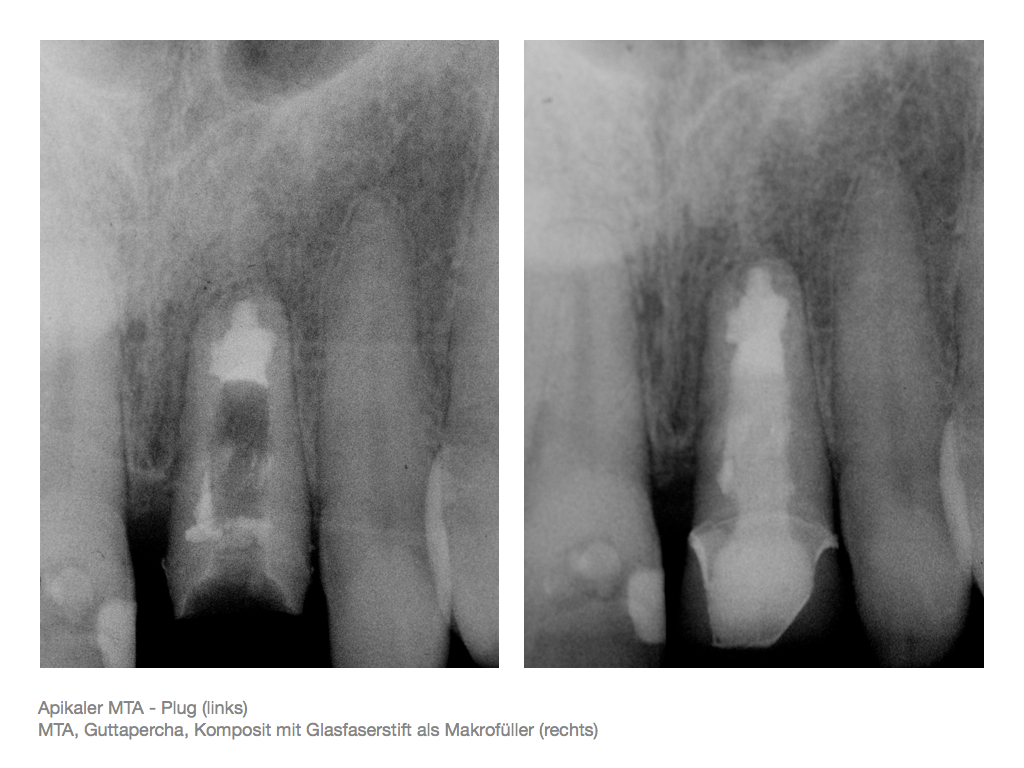

IF.070 Veröffentlicht 3. November 2012 am 1024 × 768 in Zahnerhalt „austherapierter“ Zähne durch endochirurgische Maßnahmen